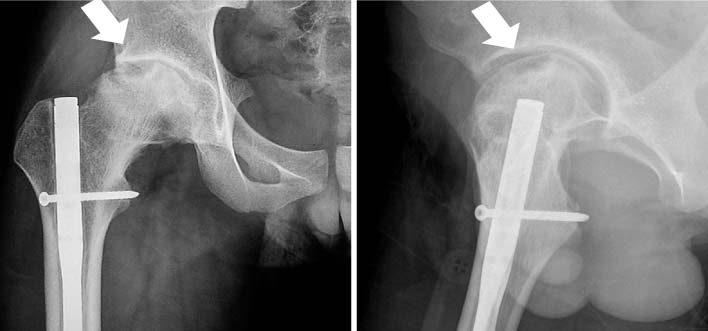

Fig. 4

After the rigid interlocking nailing of femoral shaft fracture in an adolescent, an osteonecrosis of the femoral head occurred (arrow). This picture was from the courtesy of Dr. Byun Young-Soo in Daegu Fatima Hospital.

Fig. 4 After the rigid interlocking nailing of femoral shaft fracture in an adolescent, an osteonecrosis of the femoral head occurred (arrow). This picture was from the courtesy of Dr. Byun Young-Soo in Daegu Fatima Hospital.